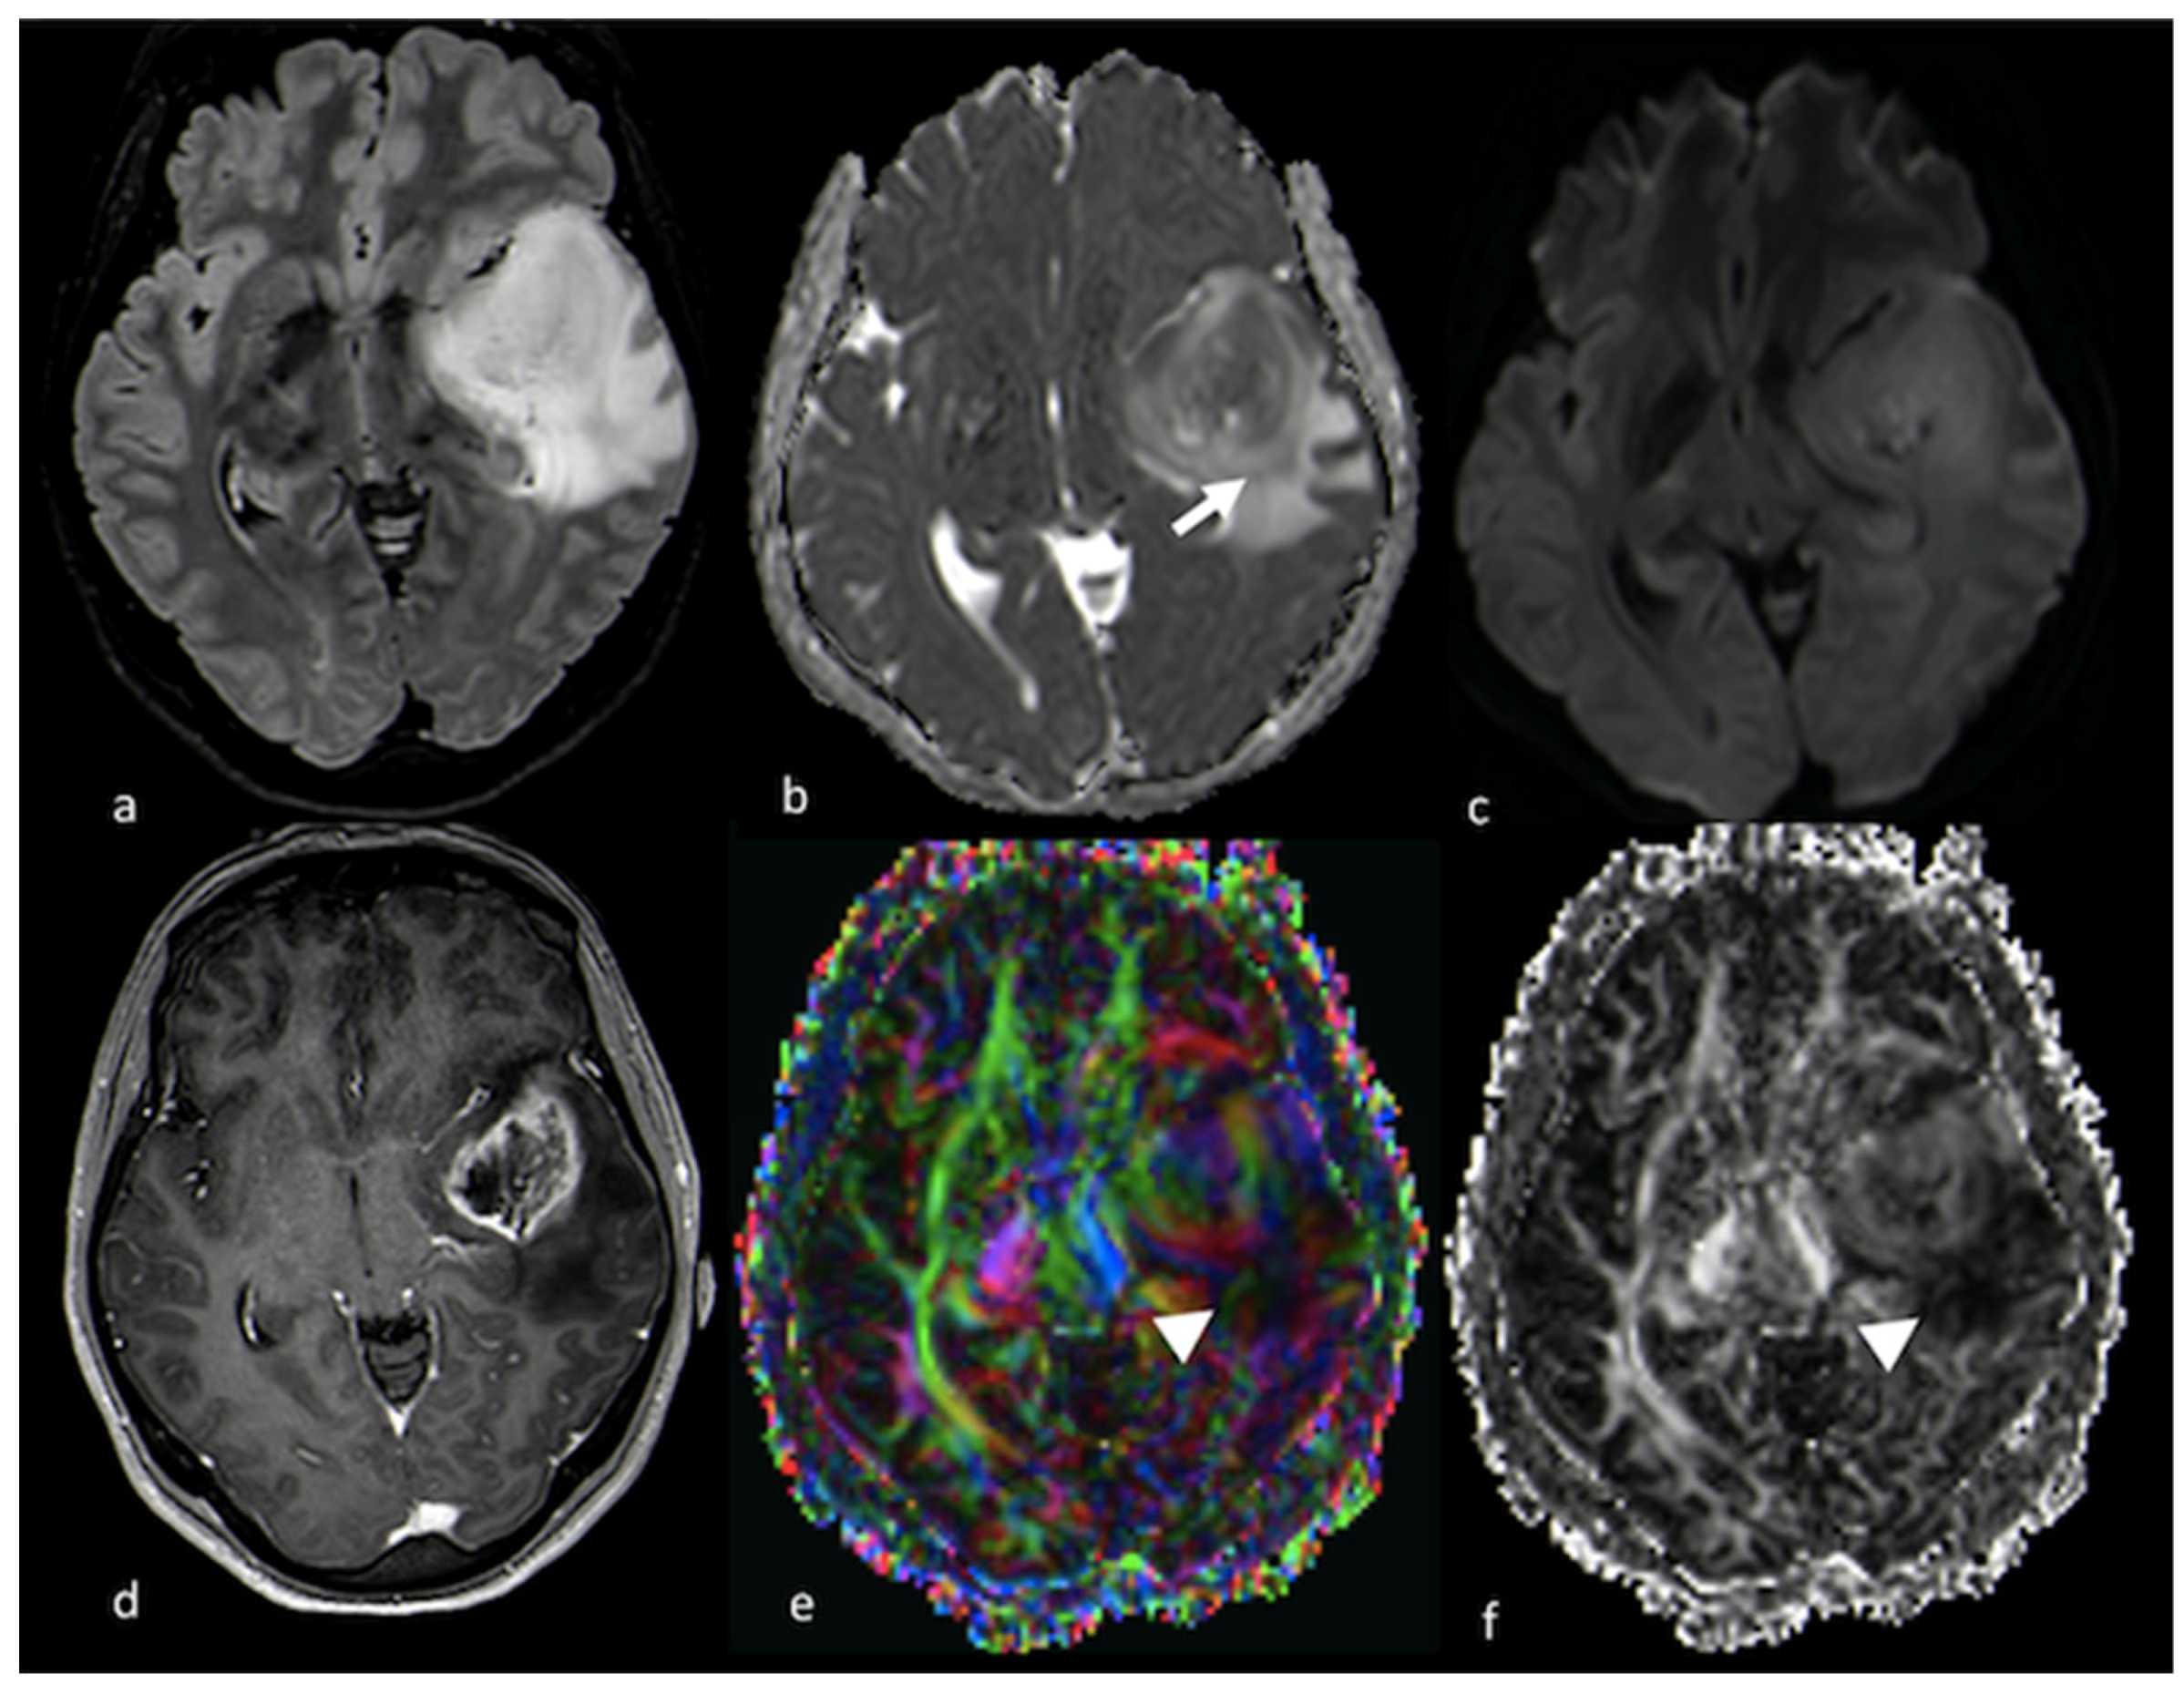

3.2.2. Diffusion Tensor Imaging (DTI)

3.2.3. Diffusion Kurtosis Imaging (DKI)

- Byrnes, T.J.; Barrick, T.R.; Bell, B.A.; Clark, C.A. Diffusion tensor imaging discriminates between glioblastoma and cerebral metastases in vivo. NMR Biomed. 2011, 24, 54–60. [Google Scholar] [CrossRef] [PubMed]

- Sternberg, E.J.; Lipton, M.L.; Burns, J. Utility of diffusion tensor imaging in evaluation of the peritumoral region in patients with primary and metastatic brain tumors. AJNR Am. J. Neuroradiol. 2014, 35, 439–444. [Google Scholar] [CrossRef]